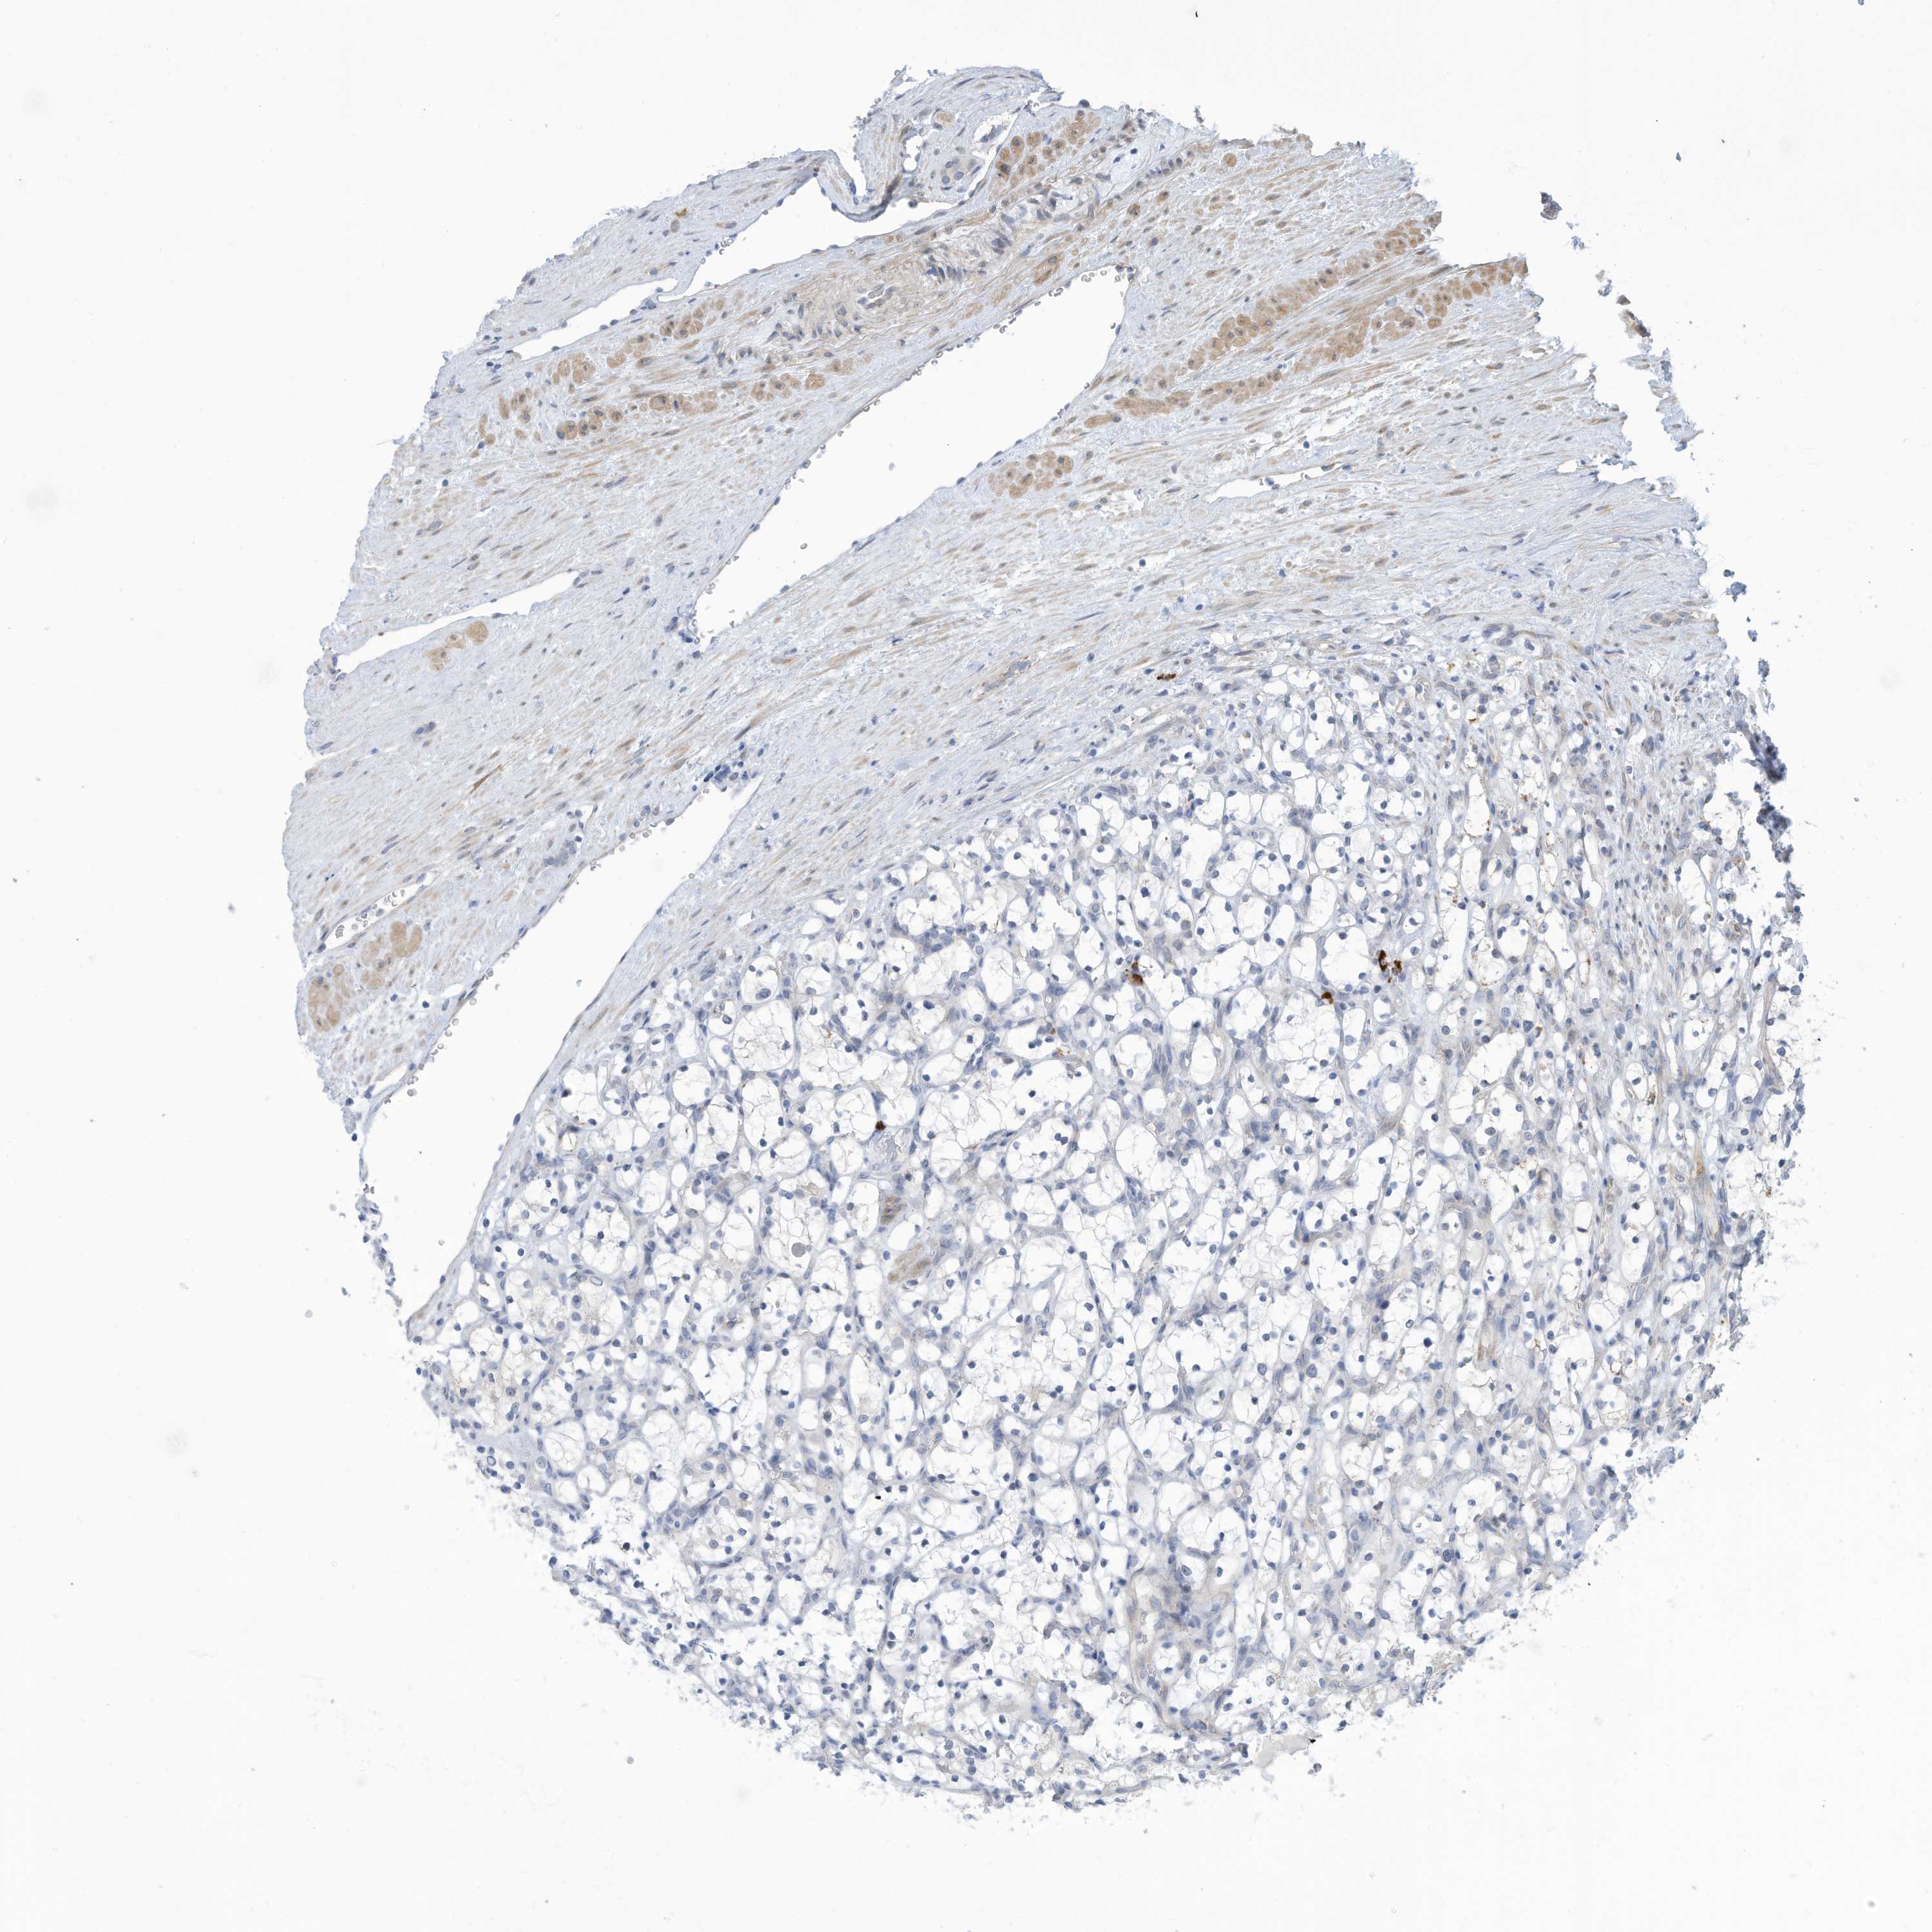

KIDNEY RENAL CLEAR CELL CARCINOMA (TCGA) - Interactive survival scatter ploti

The Survival Scatter plot shows the clinical status (i.e. dead or alive) for all individuals in the patient cohort, based on the same data that underlies the corresponding Kaplan-Meier plots. Patients that are alive at last time for follow-up are shown in blue and patients who have died during the study are shown in red.

The x-axis shows the expression levels (FPKM) of the investigated gene in the tumor tissue at the time of diagnosis. The y-axis shows the follow-up time after diagnosis (years). Both axes are complimented with kernel density curves demonstrating the data density over the axes. The top density plot shows the expression levels (FPKM) distribution among dead (red) and alive patients (blue). The right density plot shows the data density of the survived years of dead patients with high and low expression levels respectively, stratified using the cutoff indicated by the vertical dashed line through the Survival Scatter plot. This cutoff is automatically defined based on the FPKM cutoff that minimizes the p-score. The cutoff can be changed by dragging the vertical line or by entering a cutoff value in the square labeled "Current cut-off".

Under the Survival Scatter plot the p-score landscape (black curve; left axis) is shown together with dead median separation (red curve; right axis). Dead median separation is the difference in median mRNA expression between patients who have died with high and low expression, respectively. It is calculated as follows: median FPKM expression of dead patients with high expression - median FPKM expression of dead patients with low expression. This is intended to aid the user in visually exploring custom cutoffs and the associated p-scores and dead median separation.

Individual patient data is displayed and can be filtered by clicking on one or more of the category buttons on the top of the page. Categories describing expression level and patient information include: high, low, alive, dead, female, male and tumor stages. The scale of the x-axis can be toggled between linear and log-scale by clicking on the "x log" button. Mouse-over function shows TCGA ID, patient information and mRNA expression (FPKM) for each patient.

& Survival analysisi

Kaplan-Meier plots summarize results from analysis of correlation between mRNA expression level and patient survival. Patients were divided based on level of expression into one of the two groups "low" (under cut off) or "high" (over cut off). X-axis shows time for survival (years) and y-axis shows the probability of survival, where 1.0 corresponds to 100 percent.

ZNF292 is validated prognostic, high expression is favorable in Kidney Renal Clear Cell Carcinoma (TCGA)

Best expression cut offi

Based on the FPKM value of each gene, patients were classified into two groups and association between prognosis (survival) and gene expression (FPKM) was examined. The best expression cut-off refers the FPKM value that yields maximal difference with regard to survival between the two groups at the lowest log-rank P-value. Best expression cut-off was selected based on survival analysis .

When clicking on this number, the vertical dashed line indicating cut-off, the interactive survival plot, and the Kaplan-Meier curve will be adjusted to show results based on the best expression cut-off.

: 13.91

TCGA RNA samplesi

RNA-seq data is reported as average FPKM (number Fragments Per Kilobase of exon per Million reads), generated by the The Cancer Genome Atlas (TCGA) .

Normal distribution across the dataset is visualized with box plots, shown as median and 25th and 75th percentiles. Points are displayed as outliers if they are above or below 1.5 times the interquartile range. FPKM values of the individual samples are presented next to the box plot.

Average pTPM 9.9

Number of samples 521